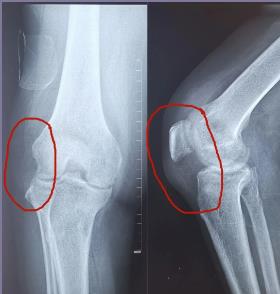

近日淄博市第四人民医院骨二组成功为一例类风湿性关节炎患者成功实施关节置换术。患者因类风湿性关节炎,多年来膝关节不能伸直,关节反复肿胀,行走受限,疼痛无时无刻不在折磨着他,不仅无法工作并且严重影响生活质量。患者入院后,骨科手术团队仔细为患者行体格检查,制定详细的手术方案,术后在骨二组医护人员的精心治疗和护理下,术后五周,患者的双膝基本活动自如。

类风湿性关节炎是一种以关节病变为主的慢性全身自身免疫性疾病。主要临床表现为小关节滑膜所致的关节肿痛,继而软骨破坏、关节间隙变窄,晚期因严重骨质破坏、吸收导致关节僵直、畸形、功能障碍。在我国类风湿性关节炎的患病率为0.24-0.5%,女性多于男性,约2-3:1,任何年龄均可发病,以20-50岁最多。本病多为一种反复发作性疾病,致残率较高。

随着我国人口老龄化的进程,各类膝关节疾患的发病率呈逐年递增趋势,但在患者看来,膝关节置换手术是“换骨”的大手术,排斥手术,到处寻医问药、保守治疗,钱没少花,罪没少受,大部分患者在病痛忍无可忍的时候,在膝关节已经严重畸形的情况下,才考虑行关节置换手术,不仅增加了手术的难度,也增加了手术后远期疗效的不确定性。

膝关节置换手术对晚期大关节畸形和功能障碍的患者行关节置换手术治疗是最终有效恢复正常生活及提高生活质量的有效治疗手段。